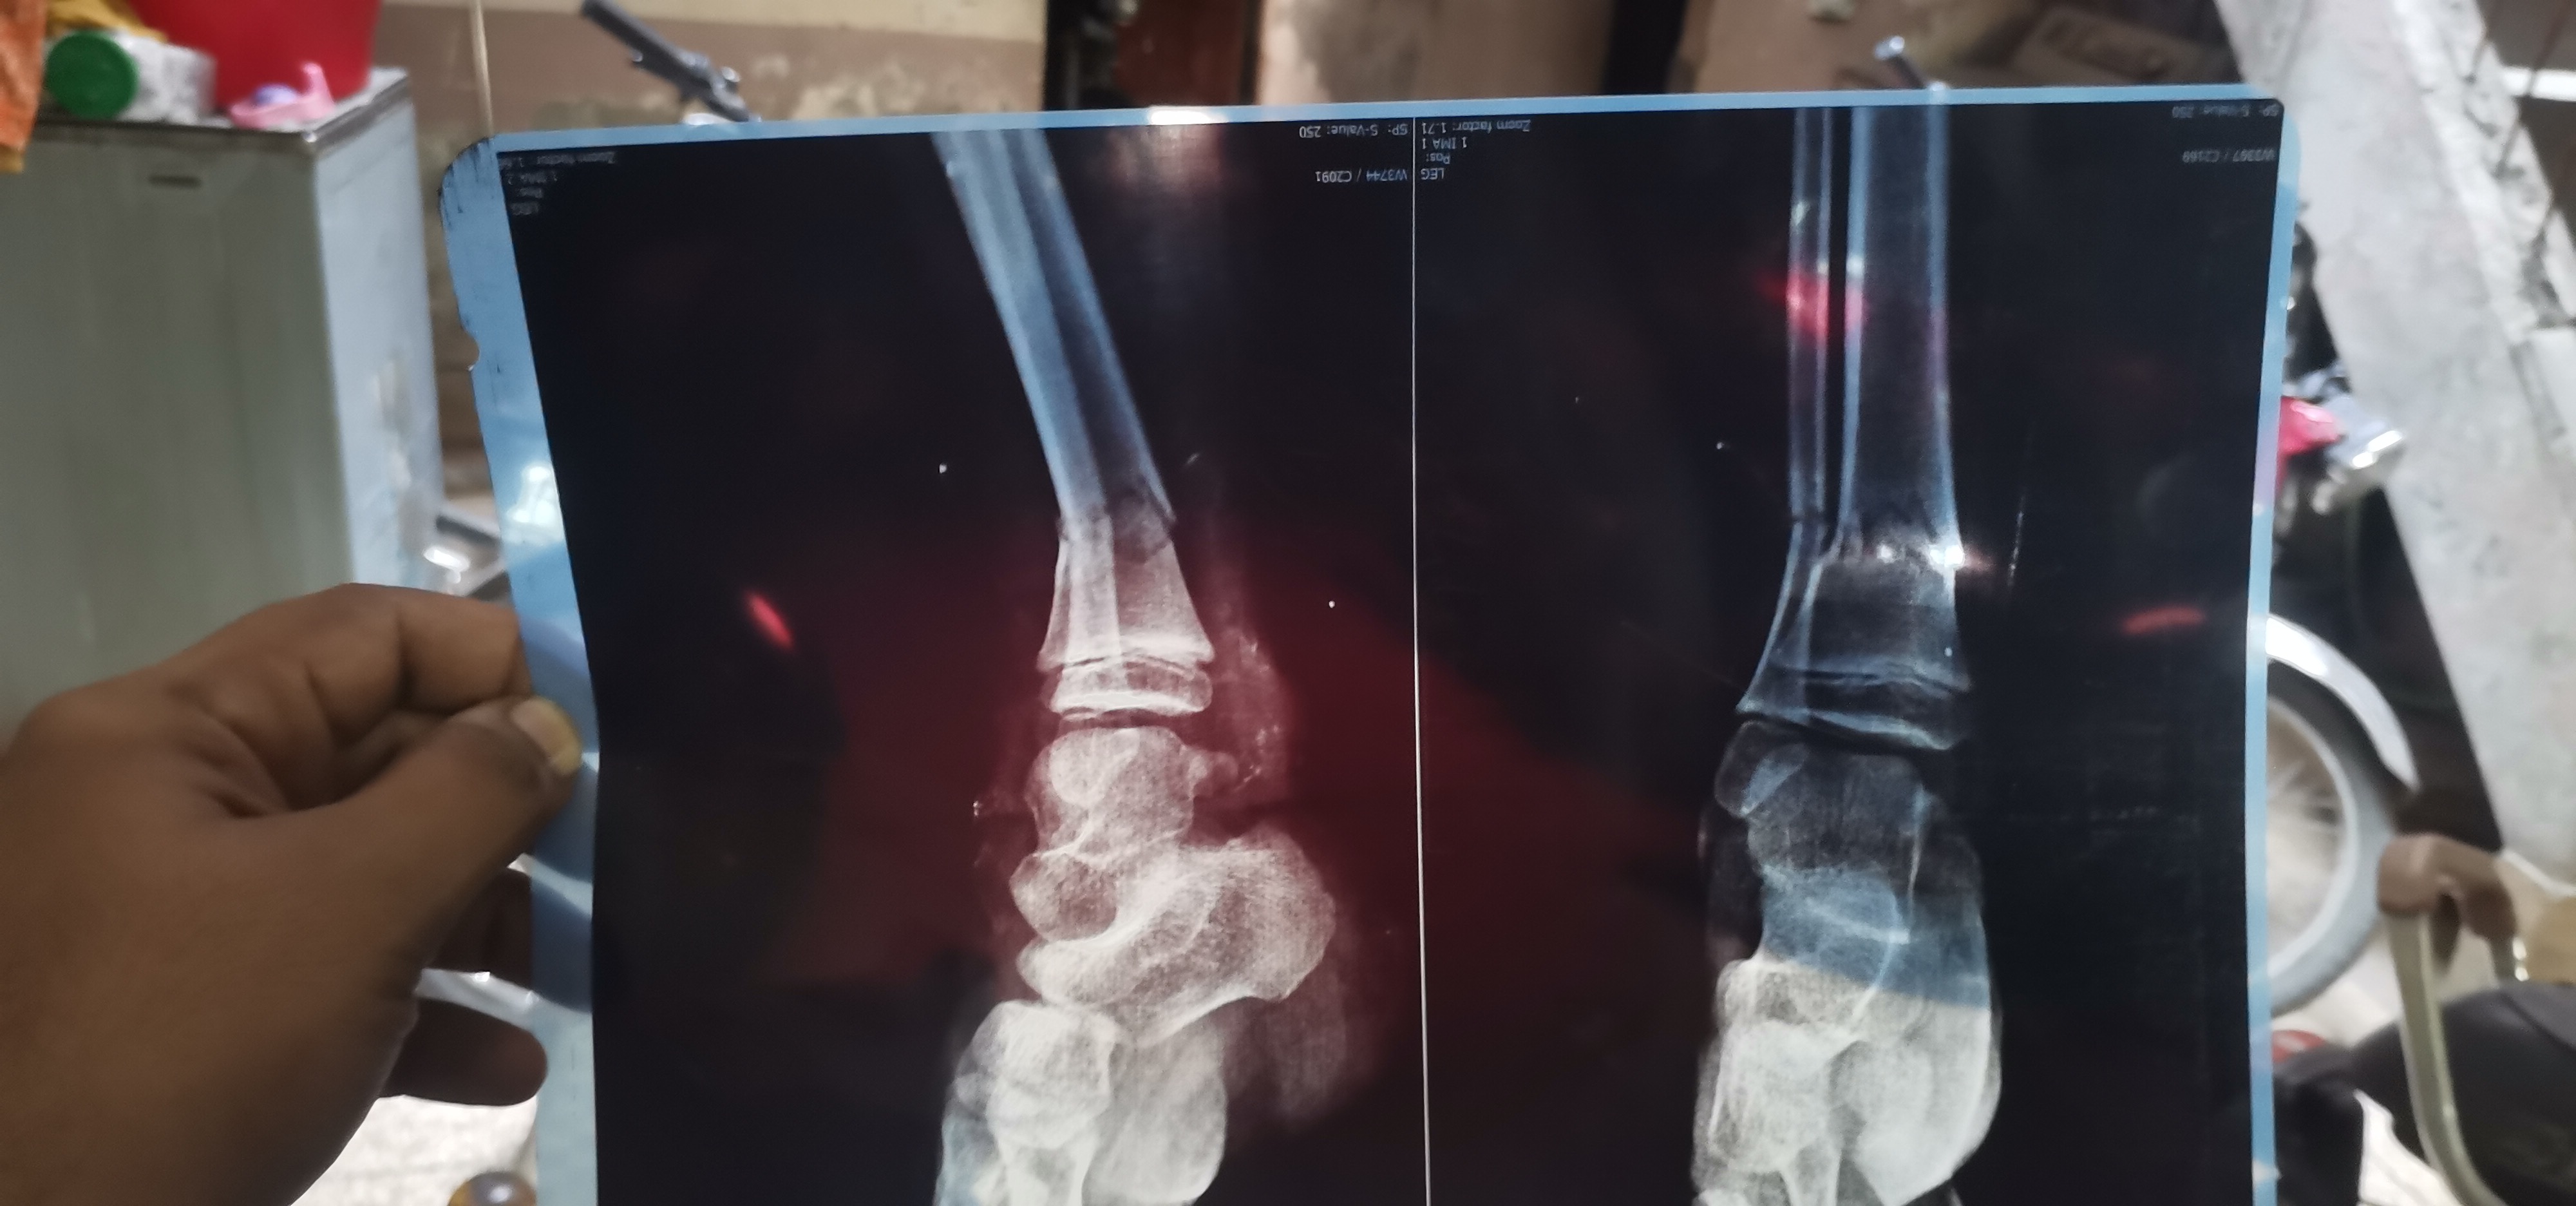

tuqeer sir meri daughter ki leg bone brake ho gai ha.. Ap ya x ray dakh kar batain plaster braber hoa .. Operate ki to zarurat Ki age 7 year ha

pop cast for 5 weeks need no surgery

plaster is enough, can you please send me new Xrays after 2 weeks to see the progress, is this plaster is above knee

plaster